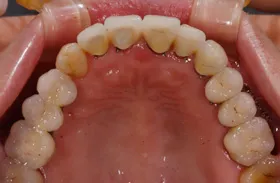

生まれつき歯が生えてこなかったケース

■治療前:生まれつき下顎左右前歯がなく隙間がある

■治療後:矯正治療後、下顎左右3番の2本にインプラント治療

| 主訴 | 生まれつき歯がなく隙間があり、審美障害・咀嚼機能障害がある |

|---|---|

| 治療方法 | インプラント治療 + 矯正治療 |

| 治療期間 | インプラント治療 約6ヶ月 |

| 通院回数等 | インプラント治療 約6回 |

| 費用 | 約94万円(税込) |

| リスク・副作用 | 術後の腫れ・痛み |